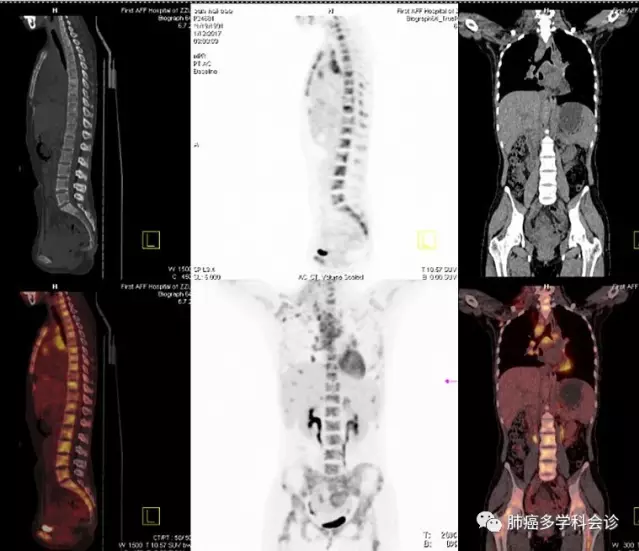

全身PET-CT示:

右肺中叶结节代谢活跃,考虑肺癌;颈部、纵隔、双肺门、右侧腋窝及前胸壁肌间多发淋巴结肿大代谢活跃,双侧肾上腺结节代谢较活跃,全身骨骼多处代谢活跃灶,考虑转移。